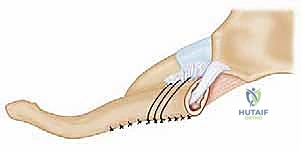

The surgical approach to the sternoclavicular joint requires a deep respect for the surrounding soft tissue envelope and the underlying vascular structures. A transverse or slightly curvilinear "hockey stick" incision is typically employed. The incision begins over the medial aspect of the clavicle, extending medially across the SC joint and curving slightly inferiorly over the midline of the manubrium. This provides excellent exposure of both the clavicular and sternal footprints of the capsular ligaments.

Dissection proceeds sharply through the subcutaneous tissue to the level of the platysma. The platysma is divided in line with the incision. Immediately deep to the platysma, the surgeon must be hyper-vigilant for the anterior jugular vein. This vessel is highly variable; if encountered, it should be carefully mobilized and retracted, or definitively ligated and divided to prevent massive hemorrhage during the deeper dissection. The medial fascia of the pectoralis major and the clavicular head of the sternocleidomastoid are identified. A subperiosteal dissection technique is strictly utilized to elevate these muscle attachments off the medial clavicle and the manubrium. Elevating full-thickness flaps preserves the vascularity of the bone and provides robust tissue for later closure.

Once the joint is exposed, the pathology is assessed. In an acute setting, the torn remnants of the anterior and posterior capsule are identified and tagged with heavy non-absorbable sutures. If the intra-articular disc is irreparably torn or blocking reduction, it may be excised, though preserving it is preferable if possible. Reduction of the joint is then performed under direct visualization. For a posterior dislocation, a bone hook or a robust towel clip is placed around the medial clavicle to pull it anteriorly and laterally, while an assistant applies lateral traction to the abducted arm.

The graft is then passed in a figure-of-eight configuration. Suture passing wires or curved shuttles are used to navigate the graft through the osseous tunnels. The graft is tensioned with the clavicle held in anatomical reduction (often requiring downward and posterior pressure on the medial clavicle). The graft limbs are then sutured to themselves and to the surrounding periosteal tissues using heavy, non-absorbable, braided sutures.

Following fixation, the previously tagged capsular flaps are repaired over the graft to provide secondary stabilization and soft tissue coverage. The sternocleidomastoid and pectoralis fascia are meticulously closed to eliminate dead space, and the skin is closed in a layered fashion.